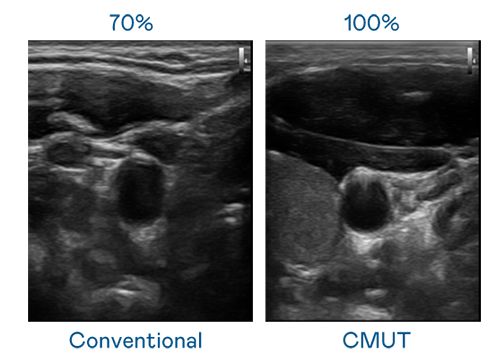

CMUT 技术是一种用电容式微机电元件来产生超音波讯号的技术。与传统 PZT 压电式技术相比,CMUT 频宽增加 30%,更宽频的超音波讯号让影像解析度大幅提升,是实现高影像品质医疗超音波扫描、促进精准医疗发展的关键技术。

超音波影像的解析度高低,首先取决于探头能发出的讯号频宽。z6尊龙官方网站 CMUT 可提供高清晰的超音波讯号,提供高频宽、高灵敏度、影像纹理细节更高的超音波影像,协助医护人员缩短影像判读时间及利用精准的医疗影像进行诊断。